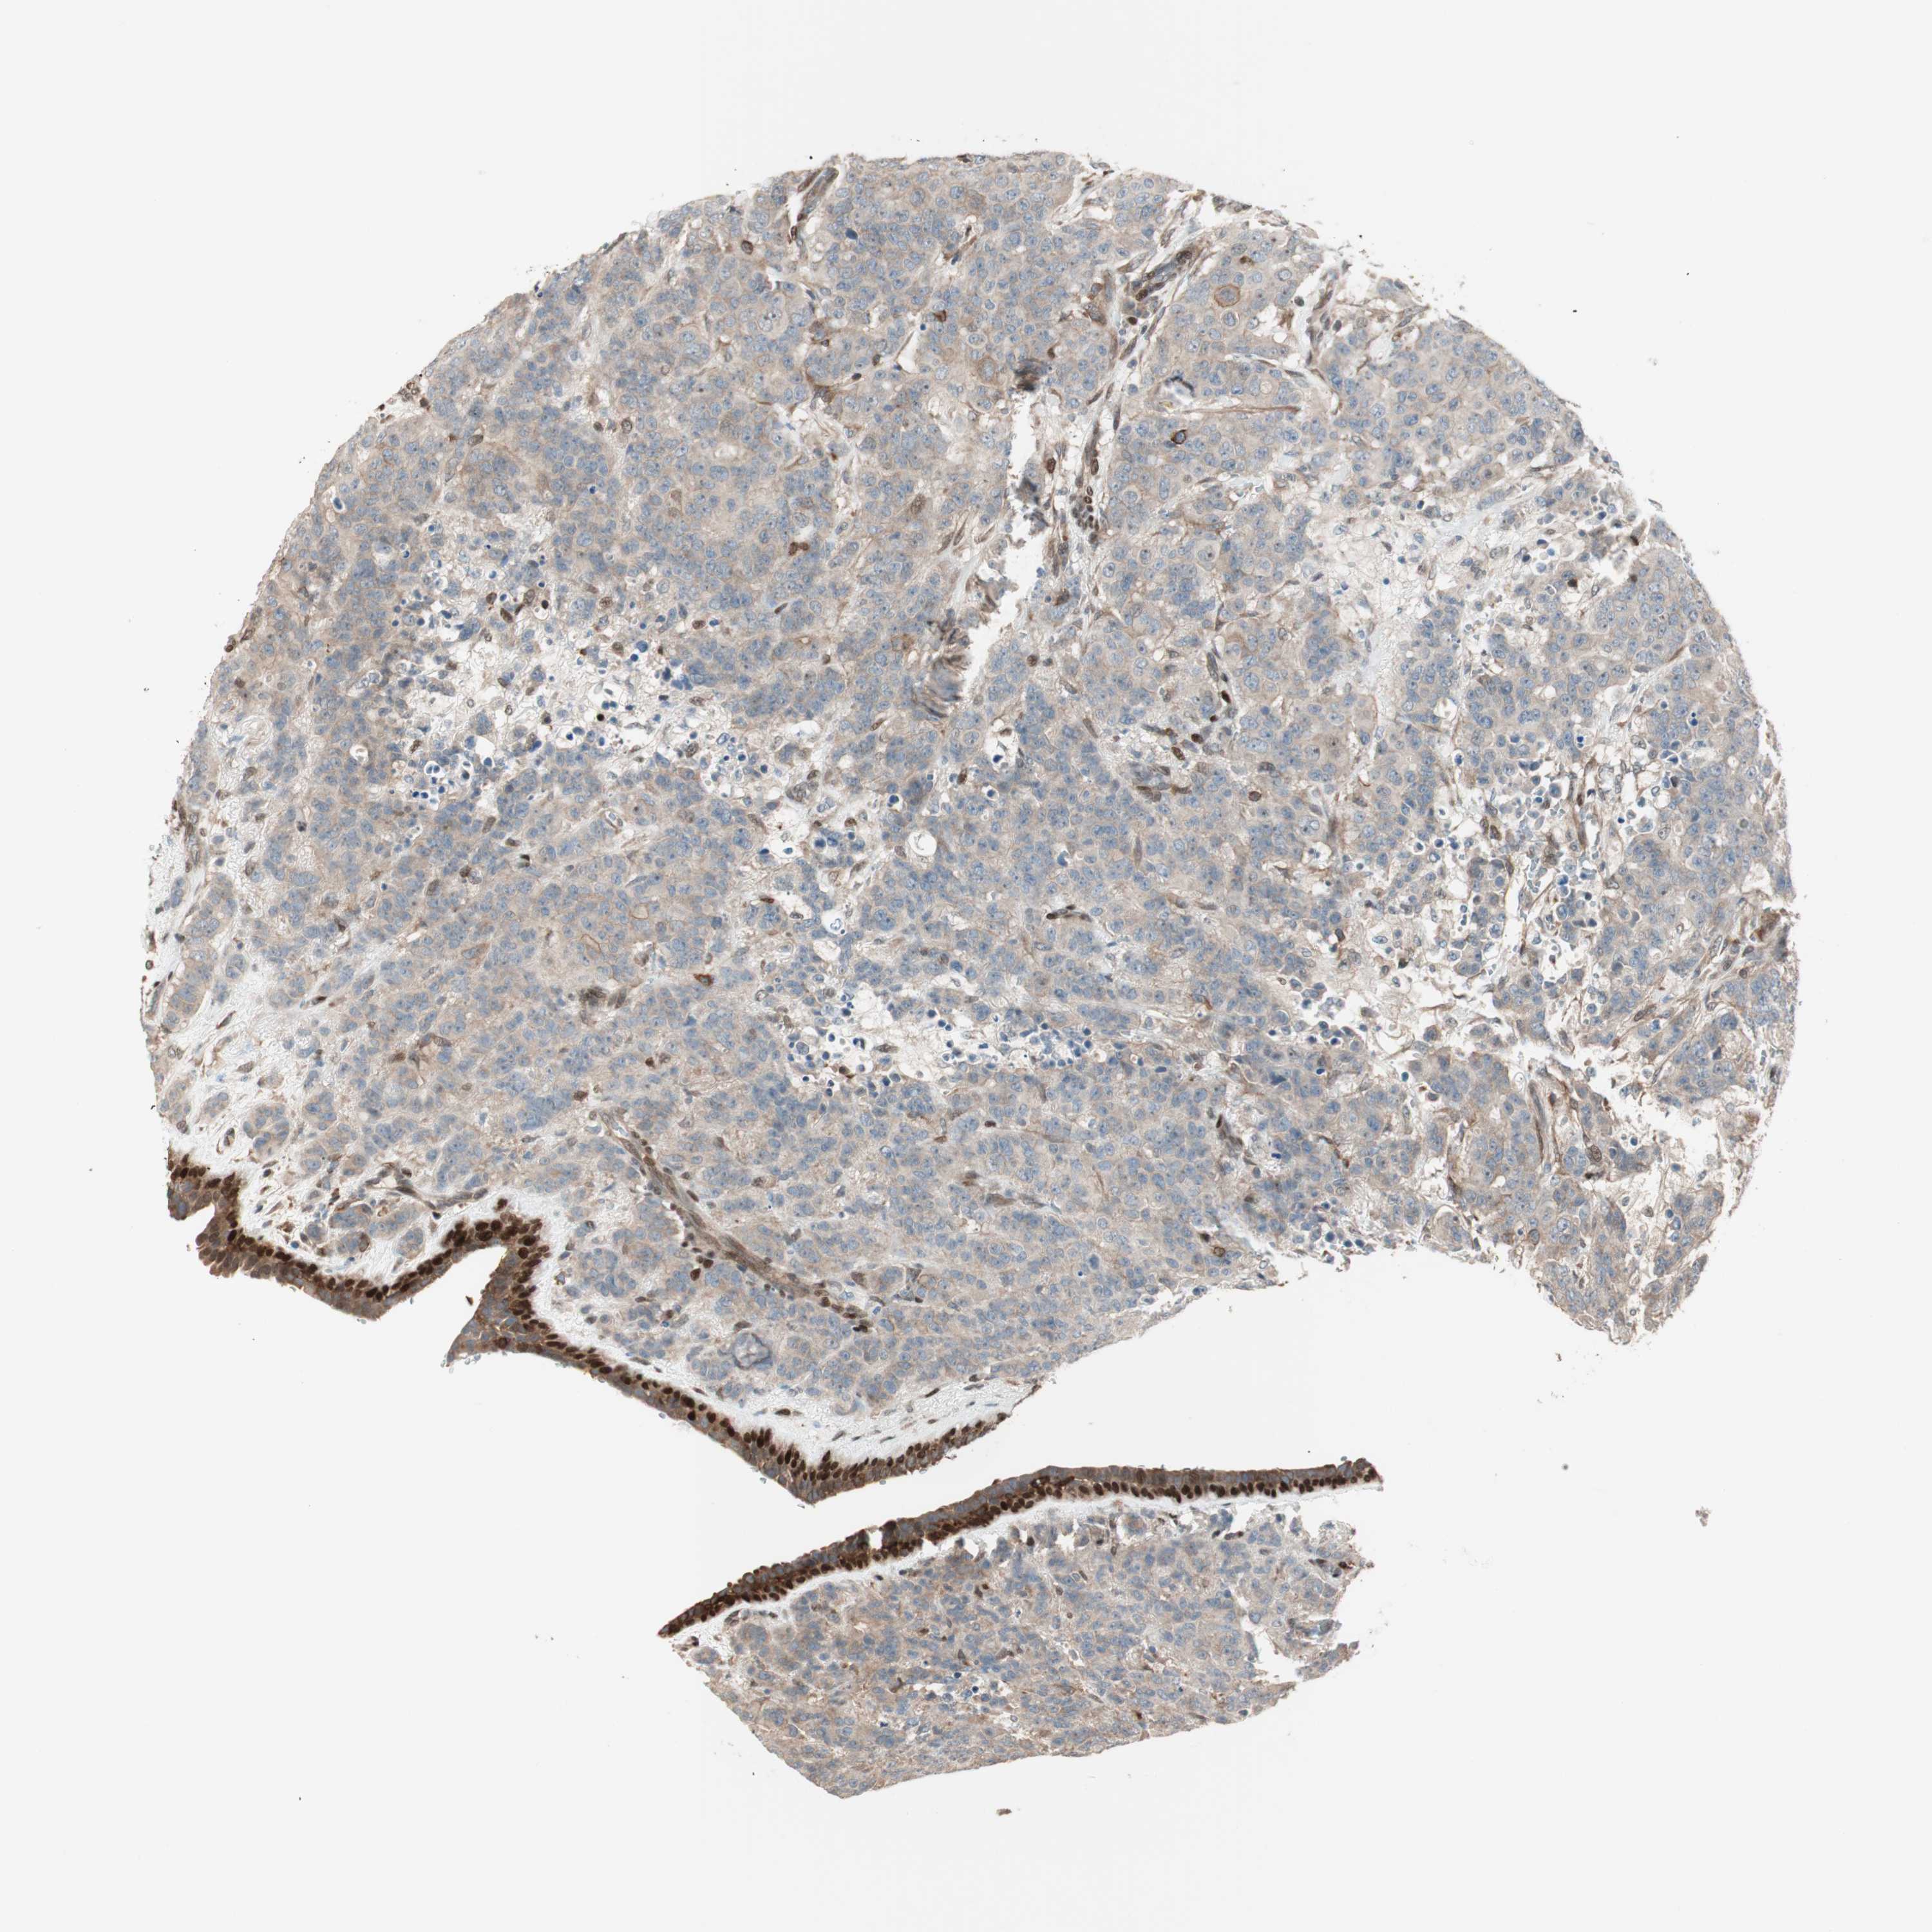

CANCER BREAST CANCER Show tissue menu

BRCA TCGA BRCA VALIDATION PROTEIN EXPRESSION